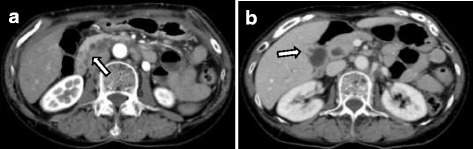

Computed tomography (CT) showed a low-density mass in the pancreatic head and thickness in the wall adjoining the gallbladder (Fig. 1a, b). Furthermore, lymph nodes around the pancreas were swelling and multiple cystic lesions with a mural nodule were found in the head of the pancreas. Magnetic resonance imaging (MRI) showed a partially cystic dilatation of the common bile duct, 32 mm in diameter, revealing that the pancreatic duct joined the common bile duct 24 mm above the papilla of Vater. The cystic dilatation of the common bile duct was classified as type Ia using the Todani system [ref. 14], and a cystic lesion in the head of the pancreas was confirmed as a branch duct-type intraductal papillary mucinous neoplasm (IPMN) (Fig. 2a, b). Positron emission tomography (PET)-CT showed an abnormal accumulation of 18-fluorodeoxyglucose (FDG) in the pancreatic head and gallbladder. The patient rejected invasive examination: therefore, we did not performed endoscopic ultrasonography (EUS) or Endoscopic retrograde cholangiopancreatography (ERCP) preoperatively.